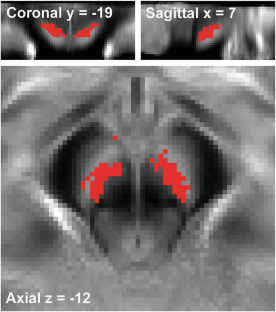

Approximately 30% of patients with schizophrenia do not respond to antipsychotics. While schizophrenia has been primarily explained by the dopamine dysfunction hypothesis, treatment-resistant schizophrenia (TRS) may involve a different pathophysiology. Neuromelanin (NM), a product of dopamine metabolism in the substantia nigra (SN), indirectly measures long-term dopamine synthesis capacity. Few studies have examined SN NM levels in TRS. Therefore, we investigated the relationship between SN NM levels and treatment responsiveness in schizophrenia. We included age- and sex-matched TRS, patients with schizophrenia in remission of positive symptoms (SZ-R), and healthy controls (HCs). Neuromelanin-sensitive magnetic resonance imaging was used to measure SN NM signals. We also evaluated clinical symptoms and cognitive impairment. We conducted voxel-wise analyses of NM contrast-to-noise ratio (CNR) to compare groups pairwise. Correlation analyses examined relationships between NM signals and symptom severity. Seventy-two participants (n = 24 per group) completed the study. The TRS group had higher dorsal SN CNR than the HC group (510 out of 1948 voxels at p < 0.05, corrected p = 0.005, permutation test). In contrast, no significant differences were observed in the other comparisons. No significant correlations were found between NM CNR and clinical severity. Our findings contrast with previous positron emission tomography studies on dorsal striatal dopamine function. Since the dorsal SN contributes to both the mesolimbic and nigrostriatal pathways, with a relatively greater role in the former, dopamine functions in these pathways may play different roles for treatment responsiveness. Further research with multimodal imaging is needed to examine dopamine function and antipsychotic treatment responsiveness in schizophrenia.